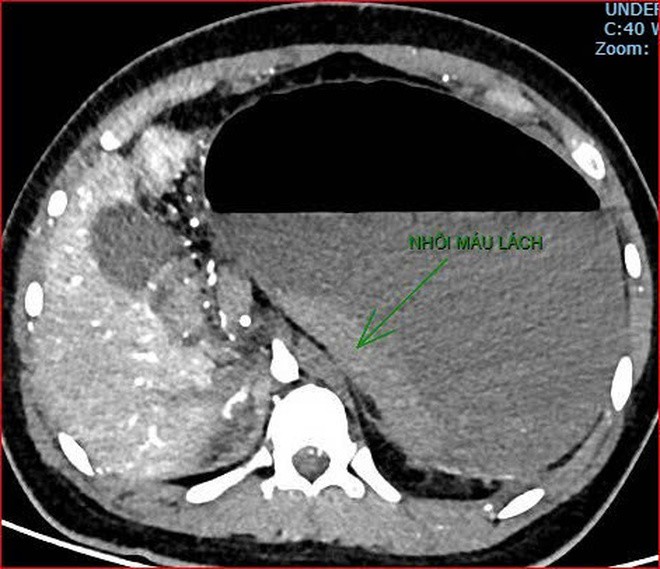

Khoảng 21 giờ 40, kết quả chụp CT cho thấy bệnh nhân rơi vào tình trạng cực kỳ nặng và hiếm gặp, bao gồm: xoắn dạ dày, nhồi máu thận trái, nhồi máu lách, viêm đầu tụy, viêm hỗng tràng, kèm dịch ổ bụng và tràn dịch màng phổi, trên nền bệnh nhân mắc hội chứng Down và tim bẩm sinh.

Hình ảnh chụp CT ổ bụng cho thấy dạ dày giãn lớn, xoắn bất thường; kèm tổn thương nhồi máu lách và viêm tụy trên nền ca bệnh hiếm, diễn biến đặc biệt nặng - Ảnh Bệnh viện cung cấp

Hình ảnh chụp CT ổ bụng cho thấy dạ dày giãn lớn, xoắn bất thường; kèm tổn thương nhồi máu lách và viêm tụy trên nền ca bệnh hiếm, diễn biến đặc biệt nặng – Ảnh Bệnh viện cung cấp